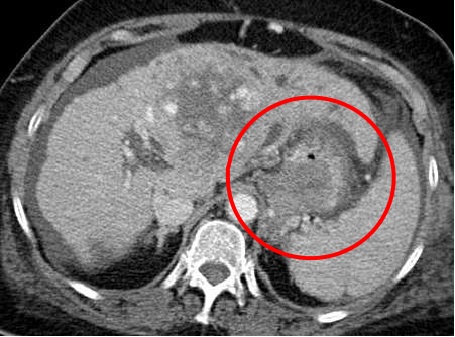

病例三女 67 MELD15 由于肝性脑病多次入院

术后第一天,Ammonia=77;患者的精神症状得到改善(A&Ox3)。术后第三天,Ammonia=60,CT大的胃肾静脉分流完全闭塞,精神状态进一步改善(A&Ox3或4) 术前

术后3天